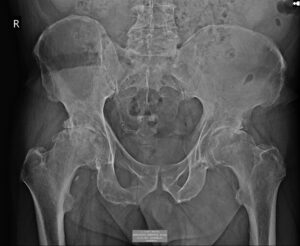

Η απλή ακτινογραφία είναι πάντοτε η πρώτη εξέταση. Δείχνει με σαφήνεια τη στένωση του μεσάρθριου διαστήματος, την παρουσία οστεοφύτων, την παραμόρφωση της κεφαλής του μηριαίου και πιθανές υποχόνδριες κύστεις. (εικόνα 4)

Είναι οικονομική, γρήγορη και παρέχει άμεσα τις βασικές πληροφορίες.

Στην ακτινογραφία παρατηρείται πλήρης συνήθως εξαφάνιση του αρθρικού διαστήματος, παραμόρφωση της κεφαλής του μηριαίου και εκτεταμένα οστεόφυτα.

Στην εικόνα 6 απεικονίζεται η ακτινογραφία ασθενούς, από το αρχείο μας, με προχωρημένη αρθρίτιτδα και των δύο ισχίων. (Ο ασθενής υποβλήθηκε την ίδια μέρα σε ταυτόχρονη αρθροπλαστική AMIS και στα δύο ισχία του)